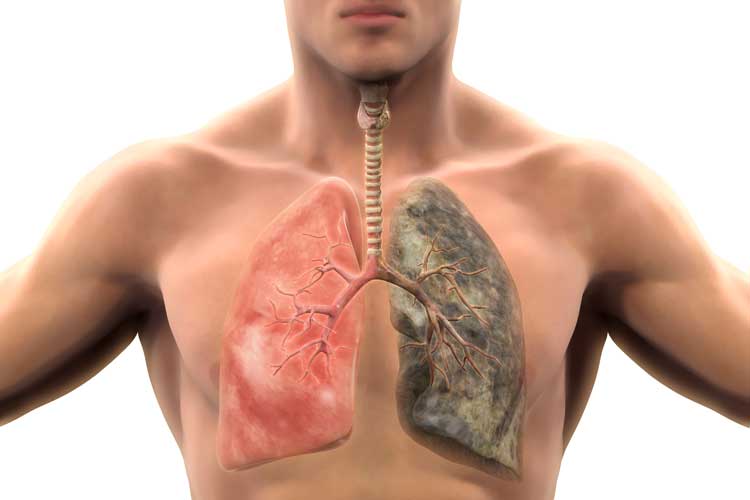

ফুসফুসের ক্যানসার প্রতিরোধ করতে ধূমপান ছেড়ে মাস্ককে সঙ্গী করুন

ধূমপান না করলেও হতে পারে ফুসফুসের ক্যানসার, রোগ দূরে রাখতে এ সব মানতেই হবে

ধূমপায়ী না হলেও হতে পারে ফুসফুসে ক্যানসার

ধূমপান ছাড়া এ সব কারণেও ফুসফুসে দানা বাঁধতে পারে ক্যানসার!